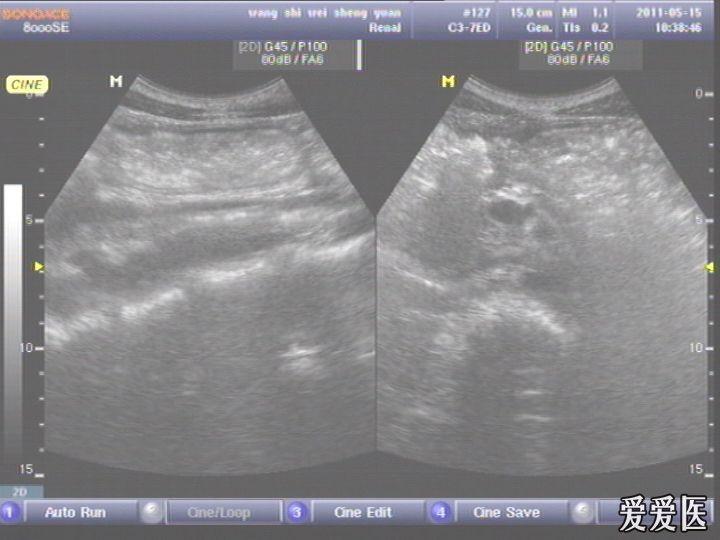

急性胃穿孔一例

患者,男,38岁,进食后突发上腹部持续性剧烈疼痛一小时来查。超声见横膈与肝之间、上腹部皮下气体强反射回声,后伴多重反射,肝前、肝肾间隙,腹腔肠管间均可见游离无回声区。直视腹部见上腹部似板样。结合病史提示“胃肠道穿孔”。急诊手术证实。

左肝外叶的那个切面如果能看到气体回声的话,那就应该高度怀疑这个病了。好切面,好好学习,太有用了,楼主辛苦感谢感谢。